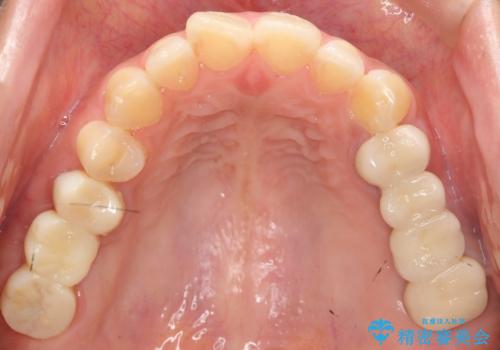

奥歯で咬むことができるようになり、また見た目も自然だと大変喜んで頂けました。

上顎骨がかなり薄くインプラント治療に対し望ましい状態でないことからも、自家歯牙移植は有意義であったと考えます。

右上奥歯の治療に関しても自家歯牙移植を希望され、現在治療中です。

被せ物の種類:メタルボンドクラウン エコノミー フルベイク